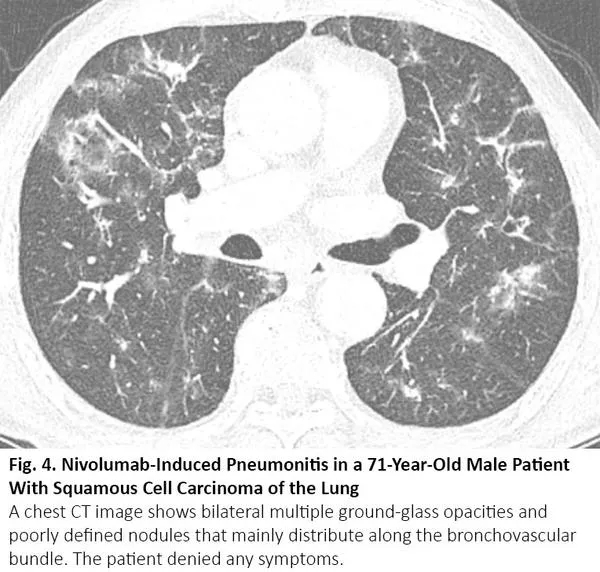

COVID-19患者的肺部CT的典型表现为双侧多发磨玻璃样影,好发于肺周3(图1)。61%~72%的COVID-19患者在症状出现后1周左右有典型CT表现,而非COVID-19患者只有不到10%人群有此类表现。4,5

图1. COVID-19患者胸部CT的典型表现

COVID-19的胸部CT可伴有局部的实质化和网状阴影(铺路石征影像表现)或其他组织性肺炎的表现,如反晕征。17% - 20%的COVID-19患者的CT与各种感染性、非感染性肺部疾病(如超敏性肺炎、肺孢子虫肺炎和弥漫性肺泡出血)难以区分(图2)。

图2. 一位67岁女性患者的胸部CT呈现COVID-19不典型特征